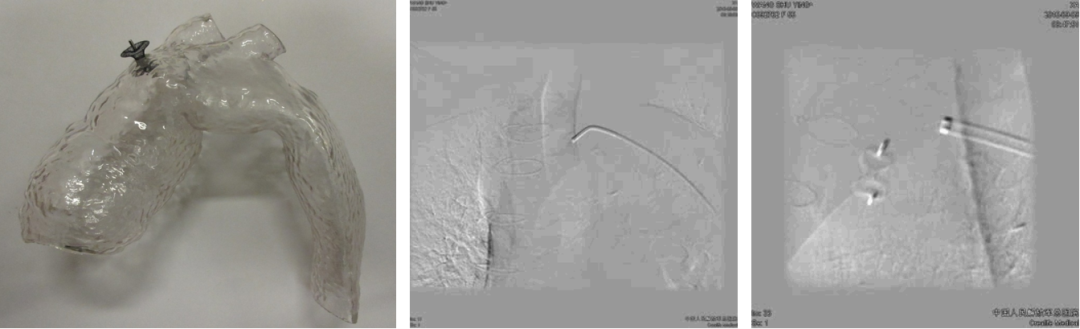

★ WeFlow-EndoSeal™假腔栓塞系统(N=11)

持续假腔血流被认为是TEVAR/EVAR术后动脉瘤样退变的原因。EndoSeal™系统是中国人民解放军总医院第一医学中心血管外科郭伟教授团队自主研发的,一种用于假腔栓塞的设备,能有效阻断假腔回流,促进主动脉重塑。

临床试验早期结果:

纳入11例患者,7例完成术后30天内CTA随访

术后30天假腔100%部分血栓化,真腔直径扩大(12.09→14.53mm),假腔最大直径稳定

1例严重不良事件(术后113天内漏栓塞)